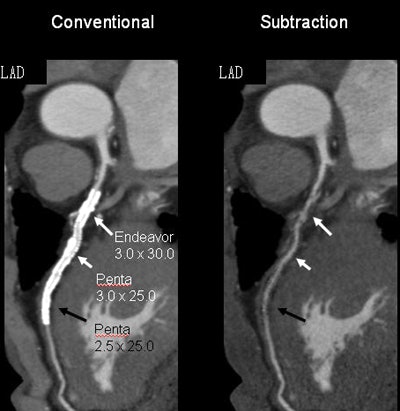

A new study of digital subtraction CT angiography (DSCTA) found that it vastly improved the visualization of the stent lumen by eliminating metallic artifacts, according to researchers from Japan. The technique was particularly effective in improving the assessment of very small stents.

Subtraction coronary CTA did a better job of visualizing the arterial lumen within metallic stents, and it also improved the evaluation of in-stent restenosis, the group reported last month at the RSNA 2014 meeting. More than 80% of stents 2.5 mm in diameter and larger can be evaluated using the technique, which also improved specificity and reduced the number of nonevaluable stents from 56 to four, the researchers found.

Fifty-six stents couldn't be assessed before subtraction, compared with four after subtraction. Among the factors causing stent nonassessability, size was by far the most important, with smaller stents harder to assess.

Still, with the use of DSCTA, stent assessability improved from approximately 78% to 92% for 3.5-mm stents (p = 0.0503), from 61% to 90% for 3.0-mm stents (p = 0.0001), and from 37% to 81% for 2.5-mm stents (p = 0.0001).

"For the larger stents, there was no statistically significant difference" in assessability with or without DSCTA, Amanuma said. However, for 2.5-mm stents, the improvement in assessability was more than 40 percentage points.